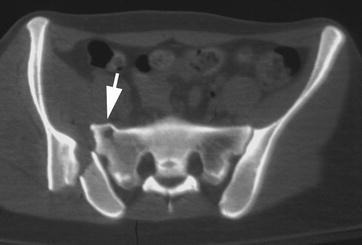

Vertical pelvic ring displacement (vprd) is a serious injury and needs assessment.

Pelvic clock® exercise device, invented by a former olympic coach, is a stretching aid for chronic lower back pain relief. Pelvic ring injury classification traditionally is made using plain radiographs. Anatomy ring structure of the pelvis • the pelvis is a true ring structure.